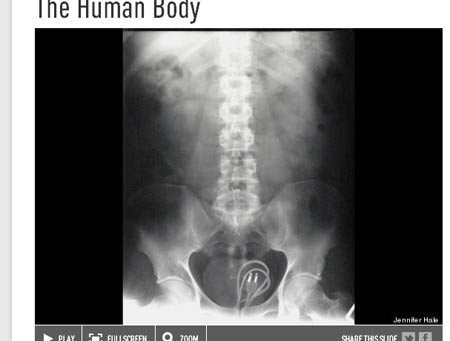

Còn người phụ nữ 37 tuổi này nói rằng cô bị trượt chân và ngã vào một chiếc bình xịt tóc.